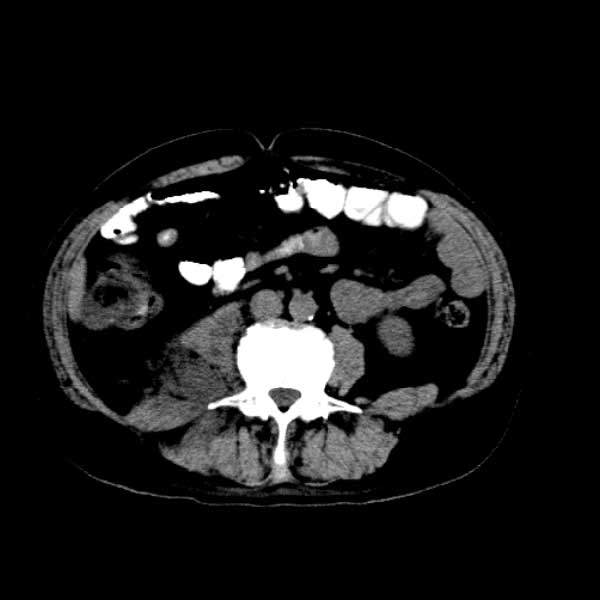

标题: CT13513:男 71 腹部疼痛20余天,近几天高热就诊,骨窗未见异 [打印本页]

标题: CT13513:男 71 腹部疼痛20余天,近几天高热就诊,骨窗未见异

考虑右侧腰大肌脓肿,向右髂窝、右腹股沟流注。

支持化脓性阑尾炎伴右髂窝脓肿、腰大肌腰方肌脓肿形成。

考虑腹腔及盆腔化脓性炎症,累及右侧髋关节及腹股沟区.

首先考虑化脓性阑尾炎伴腰大肌、腰方肌脓肿,不除外回盲部结核。

回盲部癌待排除。

患者肠镜检查考虑结肠癌,病理证实

患者肠镜检查考虑结肠癌,病理证实。肺部ct可见多发结节,考虑转移